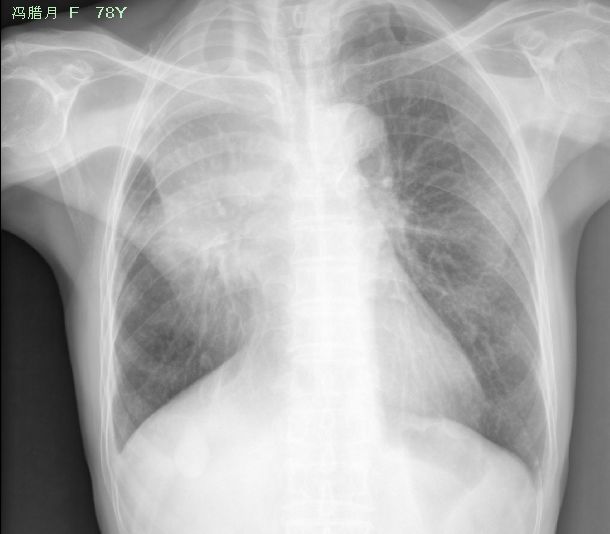

以下是引用yuhongjun在2008-8-19 17:32:00的发言:[br]右胸廓塌陷,右中上肺野密度均匀增高,纵隔尚居中,心脏形态大小正常,双膈面光滑,肋膈角锐利.[br][br][br]印象诊断:考虑右肺门占位性病变并发阻塞性肺不张,建议ct 进一步定性.

以下是引用zhangzhongshou在2008-8-19 19:41:00的发言:[br]x线表现:右侧骨性胸廓略塌陷,右肺中上野大片密度增高影,边界不清,水平裂未显示,右肺门增大,隐约显示肿块影,余肺未见异常,心脏纵隔无明显移位,右下肺野纹理稀疏,右膈面内侧升高。双肋膈角清晰,锐利。[br]诊断意见:右肺门肿块并右肺上叶肺不张,最大的可能为支气管肺癌,建议纤维支气管镜及ct检查。[br]分析:初步一看似横“s”征,仔细一看,是胸壁软组织重叠假象,没有侧位,仅凭正位看,右肺门肿块,右肺上叶不张的征象还是有的。有侧位可以更加明确,不过仍需要进一步检查确定。[br][br][本贴已被 zhangzhongshou 于 2008-8-19 19:51:23 修改过]